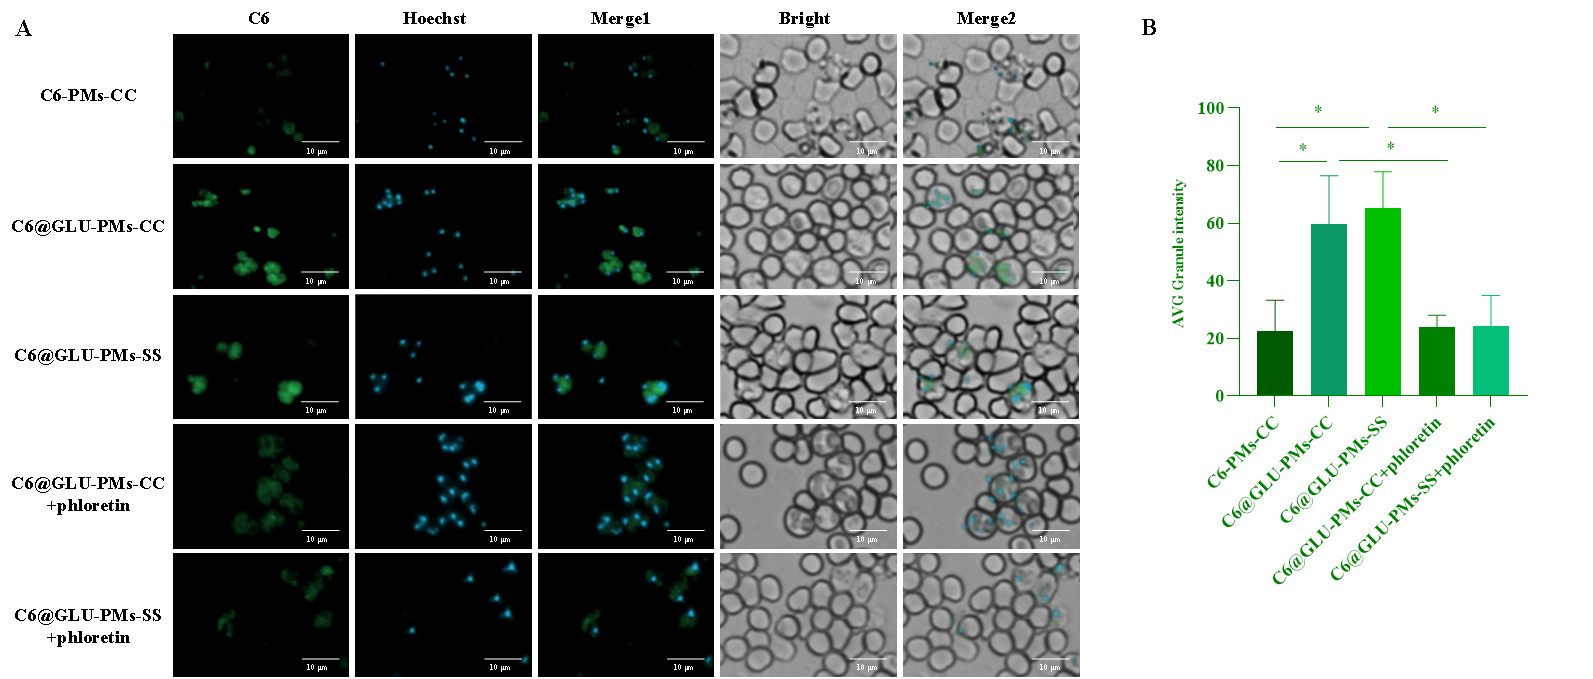

图2 C6-PMs-CC、C6@GLU-PMs-CC和C6@GLU-PMs-SS的体外靶向性(A、B)和红细胞内靶向性(C)评价(n = 3)

以香豆素6(C6)标记的无葡萄糖基修饰的非还原响应微粒(C6-PMs-CC)为对照,微粒与感染的红细胞共孵育后,葡萄糖基修饰微粒在疟原虫中的富集显著增强(P<0.05)(图2)。